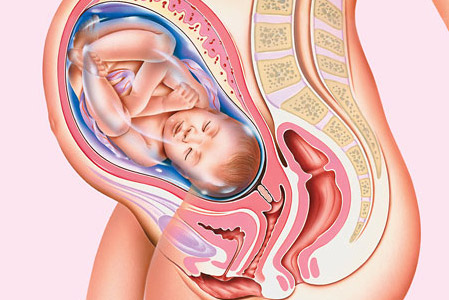

Guida gravidanza: nono mese

Ed eccoci arrivate al nono mese di gestazione, l’ultimo mese della nostra Guida gravidanza, quello che va da da 35+1 a 40 settimane: il piccolo ha riaggiunto il suo completo sviluppo e può finalmente nascere.

NONO MESE: COSA FARE

In questo mese è fondamentale prepararsi alla nascita del bambino; quanto appreso durante i corsi pre parto tornerà sicuramente molto utile.